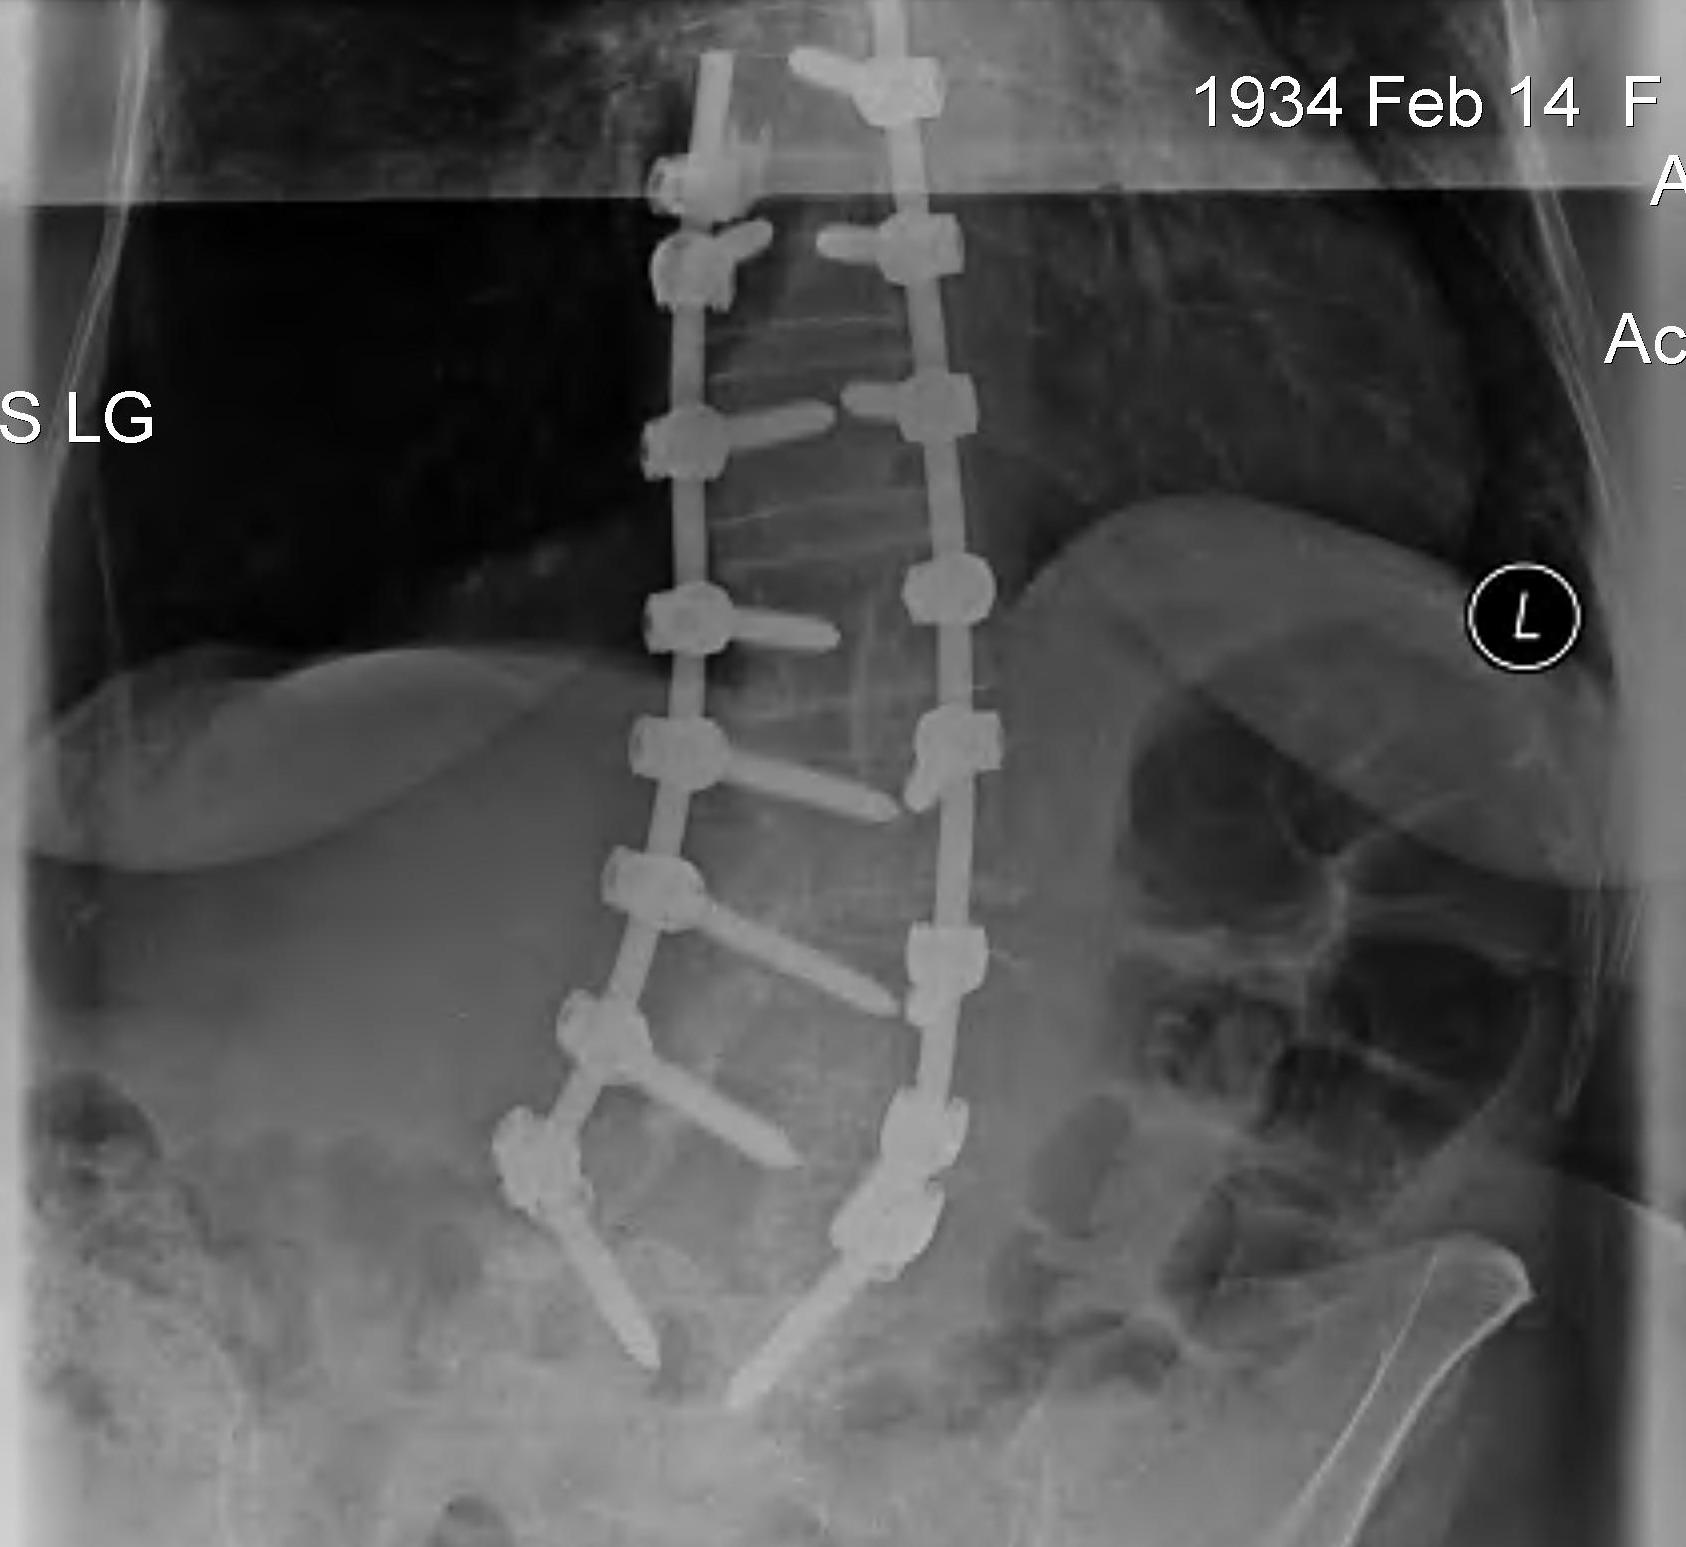

X-ray

Multilevel decompression and posterior instrumented fusion

- laminectomy / foraminotomy

- +/- interbody cages to increase foraminal size